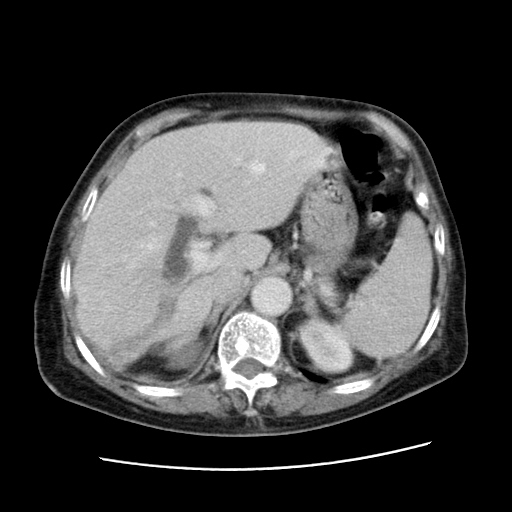

女,77.无不适

肝脏变异、异位胆囊,肝右叶肝内胆管结石并肝内胆管扩张。

肝右叶肝内胆管结石并肝内胆管扩张。

肝右叶肝内胆管结石并肝内胆管扩张

胆总管扩张

肝右叶肝内胆管结石并肝内胆管扩张。胆总管下段梗阻,考虑壶腹部占位。

右侧肝内胆管局限性扩张,其内密度不均匀,扩张的胆管壁增厚,考虑肝内胆管炎合并结石可能性大